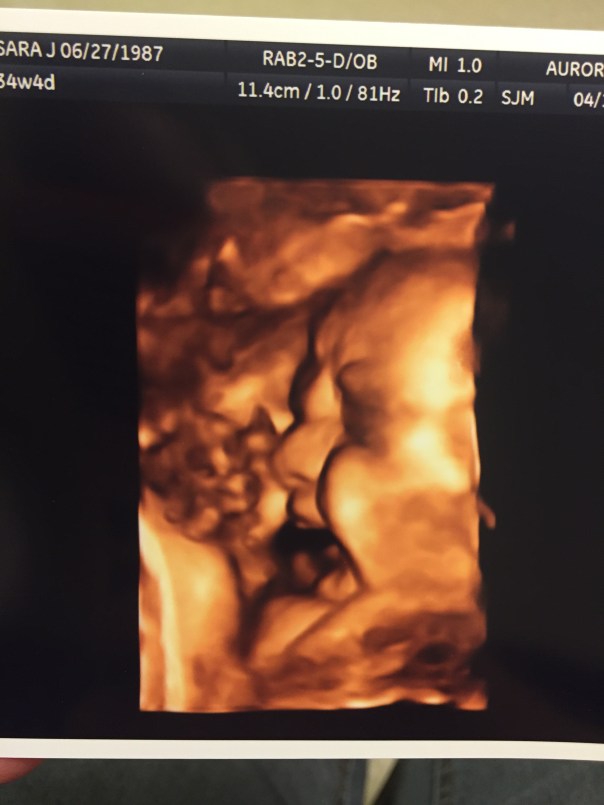

I LOVE this gift. We didn’t know Elijah’s gender yet, but I thought it was just splendid to add this ornament to the tree because it was exactly what our family looked like in 2016.